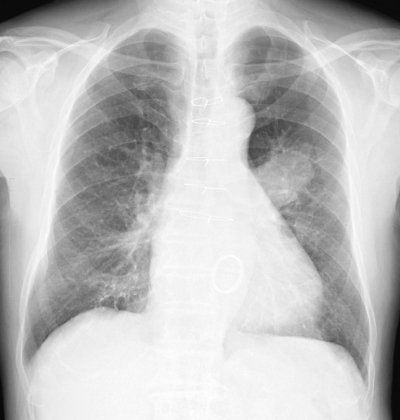

体温 36.4 ℃。脈拍 68/分、整。血圧 122/72 mmHg。呼吸数 18/分。SpO2 97 %(room air)。呼吸音に異常を認めない。血液所見:Hb 10.8 g/dL、白血球 5,400。CRP 0.9 mg/dL。肺癌治療前と今回来院時の胸部エックス線写真及び放射線治療の照射野を示す。

治療前